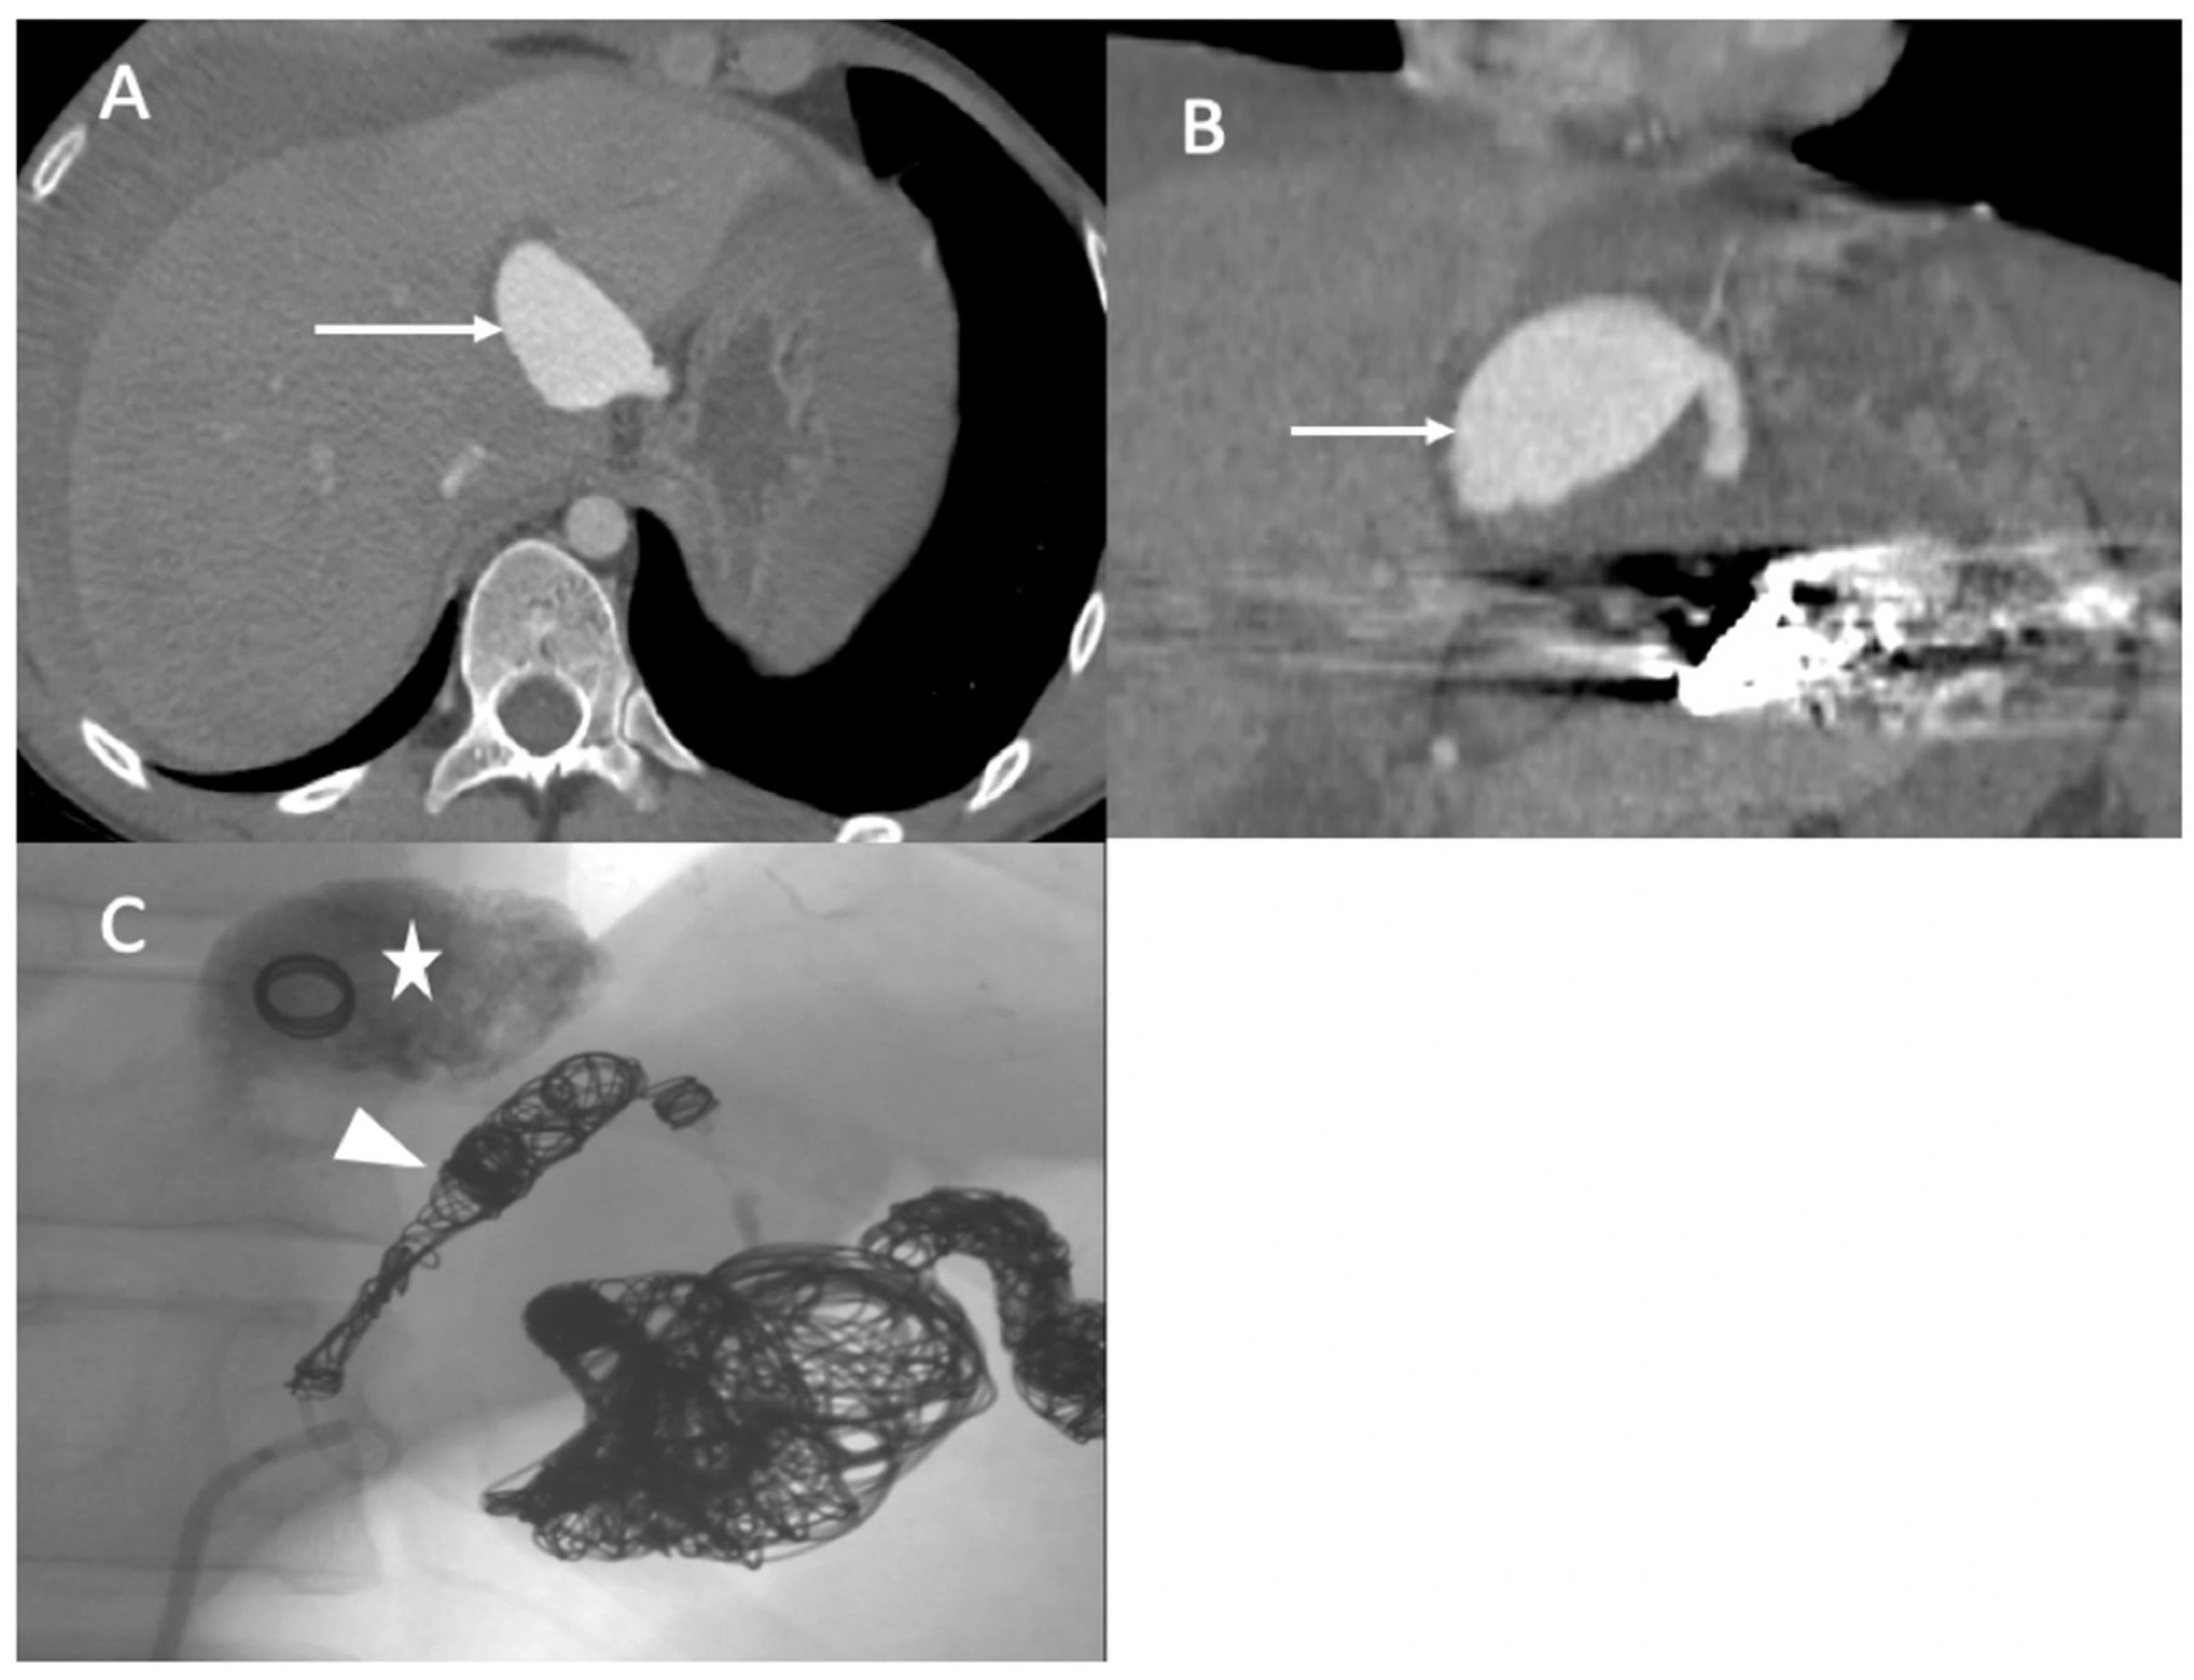

A 36-year-old female was referred to our hospital presenting with hemoptysis and respiratory distress. One week before she delivered (35 weeks gestation), she experienced hemorrhagic shock due to the rupture of a splenic artery pseudoaneurysm. She was treated by a cesarean birth and a splenectomy. The patient was managed using mechanical intubation and bilateral pleural drainage. An enhanced thoracic computed tomography (CT) scan revealed an intraparenchymal hemorrhage in the right upper lobe with an arteriovenous fistula between the apical segmental pulmonary artery and the azygos vein, as well as a pseudoaneurysm at the ostium of the middle segmental artery (Figure 1).

Figure 1.

(A) Axial image from the contrast-enhanced thoracic CT scan revealed an arteriovenous fistula between the apical segmental artery and the azygos vein (arrow); (B) coronal section of the CT scan revealed a pseudoaneurysm of the right lobe superior artery (star); (C) axial image thoracic CT scan (pulmonary window) showed bilateral pleural effusions with ground glass opacity, most likely due to pulmonary hemorrhaging.

The diagnosis of EDS was suspected based on the patient’s clinical history and CT scan findings, and endovascular management was decided with a thoracic surgeon. Under local anesthesia, a 10 F introducer sheath (Radiofocus® introducer II, Terumo Corporation, Tokyo, Japan) was inserted via the right femoral vein. The right pulmonary artery was catheterized using a 6 F ENVOY catheter (Codman-USA), and the distal segment of the arteriovenous fistula was occluded using multiple 0.035 hydrocoils (Figure 2A,B). The ostium of the arteriovenous fistula was occluded with second-generation plugs (AMPLATZER-USA) (Figure 2C), and the pseudoaneurysm was occluded using multiple 3D coils (Figure 2D).

(A,B) Before and after the occlusion of the distal portion of the arteriovenous fistula (arrow, head arrow). (C) Before the occlusion of pseudoaneurysm (star). (D) The occlusion of the proximal portion using first- and second-generation plugs (arrow), and the occlusion of the pseudoaneurysm using multiple 3D coils.